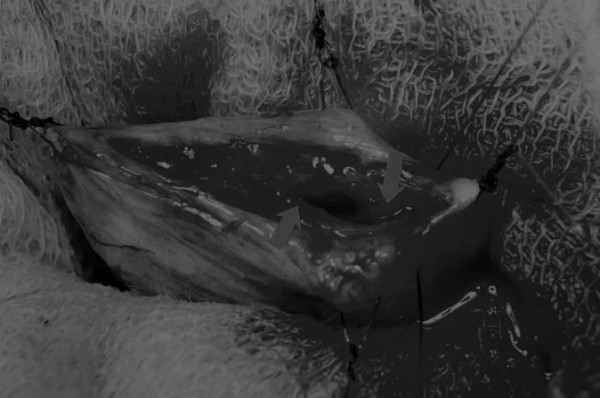

在牵引缝线之间选择血管扩张较差的区域用手术刀切开膀胱壁(图3)。在牵引缝合线之间用手术刀在血管不良的区域做切口。切开膀胱壁后,膀胱内的手术可按手术方案实施,例如取出结石(图4)。

图3 避开主要的膀胱血管,做一个尽可能小的切口

切口可以在膀胱背侧或腹侧进行,避免对大血管的损伤。